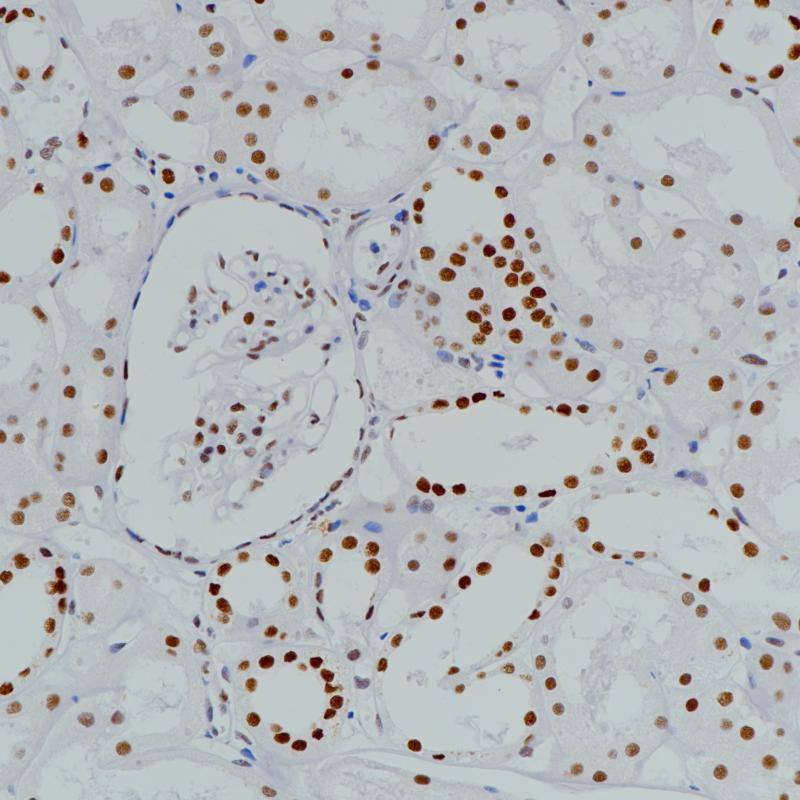

PAX-2是PAX转录因子家族成员之一,与PAX-8一起参与肾脏器官的形成。在非肿瘤组织中,PAX-2表达于肾小球壁上皮细胞,肾集合管细胞,萎缩的肾小管细胞,卵巢表层上皮细胞,输卵管,子宫颈内膜,子宫内膜。在原发性肿瘤中,PAX-2主要出现于肾细胞癌,肾原性肿瘤。近来的调查表明,PAX-2可作为有效的免疫组织化学标记物,有助于诊断肾上皮细胞瘤以及一些妇科肿瘤。

阳性对照

细胞核